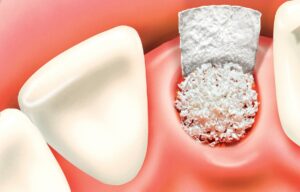

Для проведення імплантації необхідна наявність достатнього обсягу кісткової тканини. При її дефіциті буде потрібно проведення кісткової пластики. З цією метою може бути використана як власна кісткова тканина пацієнта (аутотрансплантат), так і донорський матеріал (аллотрансплантат), а також синтетичні матеріали (біокераміка, гідроксиапатит, фосфат кальцію) або ксенотрансплантати (на основі кісткової тканини тварин).

Після підняття мембрани отриманий простір між дном гайморової пазухи і мембраною заповнюється остеотропним матеріалом.

Імплантат впроваджується в це, вже підготовлене ложе після введення матеріалу.